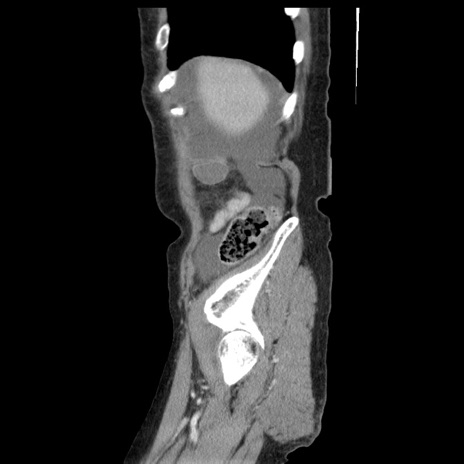

症例1(矢状断像)

【症例】80歳代女性

【主訴】腹痛

【現病歴】8時間前から腹痛あり来院。

【既往歴】糖尿病、脂質異常症、子宮体癌にて子宮全摘術

【身体所見】意識清明・会話良好だが腹痛で苦悶様、全腹部にわたって反跳痛と圧痛あり

【データ】WBC 13600、CRP 0.14、LDH 224、CK 90